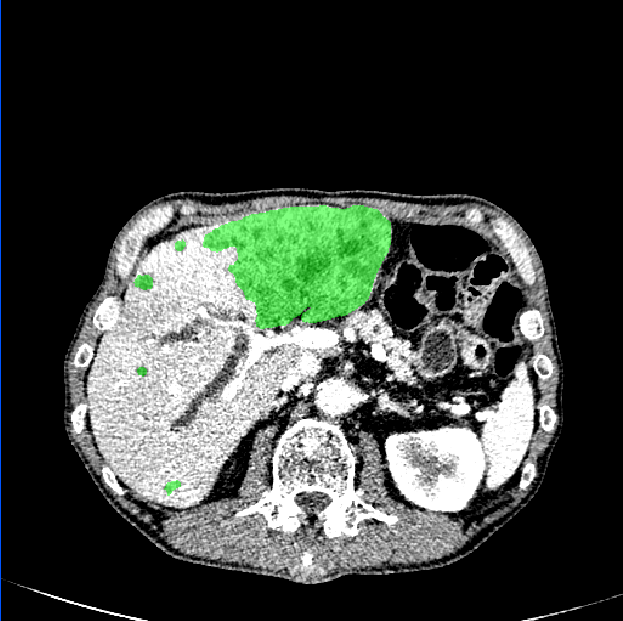

3.1 Comparison of Various Distance Maps Regression

A simple illustration of distance maps is shown in Fig. 2, which contains the binary segmentation mask, O-DM, inverse distance map (I-DM), NI-DM and sign norm inverse distance map (SNI-DM). I-DM is derived from the I-DM by taking inverse operation. SNI-DM is modified from the NI-DM, where the voxel inside the boundary of the target object is positive, otherwise is negative.

As shown in Fig. 3, our method demonstrates superior qualitative results, especially in the notoriously small tumors segmentation. In Table 1, the results show that the M-Net with the LR-Net achieves better performance than M-Net alone on all the evaluation criteria. This indicates indicates the significance of LR-Net on accuracy improvement. Then, we evaluate the performance of MapDice loss. By comparing the results with and without the MapDice loss, it is apparent that MapDice loss contributes a lot for segmentation accuracy improvement. In particular, the MapDice loss yields the superior results of NI-DM regression, while Dice loss shows a significant drop in the last four columns of Table 1. This indicates that distance map can help the network to capture semantically meaningful regions and produce more accurate reslults. The constant value , used to balance the magnitude difference of two different losses, is also verified to be effective for the performance improvement.